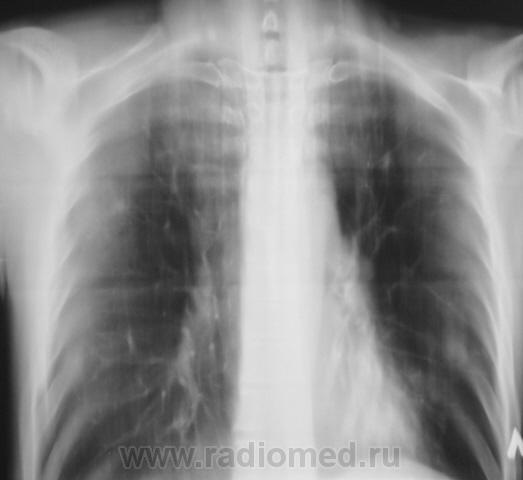

Следущий контроль (сегодня).

Осенне-весеннее обострение...